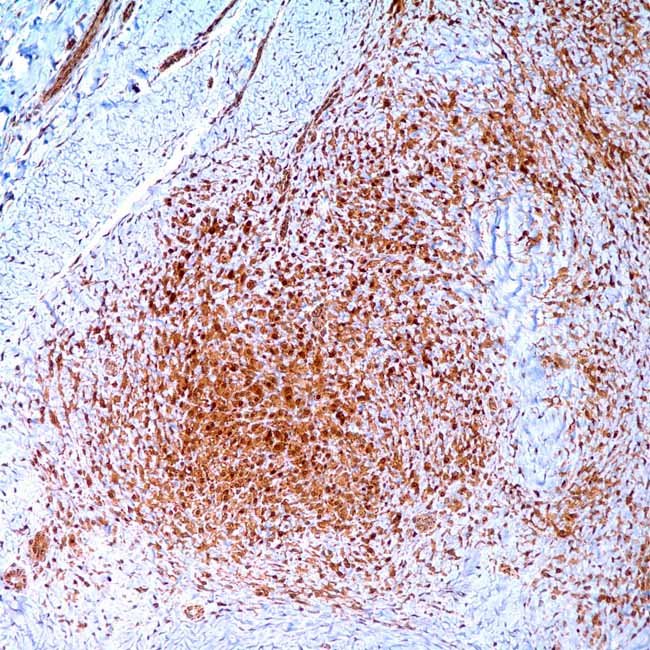

Beta – Catenin (14)

Beta-catenin is a 92 kD protein that is often present in thesub membranous region of the cell’s cytoplasm. Thisprotein accumulates in the nucleus when the beta-cateningene is mutated. This protein’s nuclear accumulation hasbeen shown in breast and abdominal fibromatosis(desmoid tumours), which helps distinguish it from otherspindle cell neoplasms that might develop there.

VisualisationNuclear, membranous

ControlFibromatosis of breast